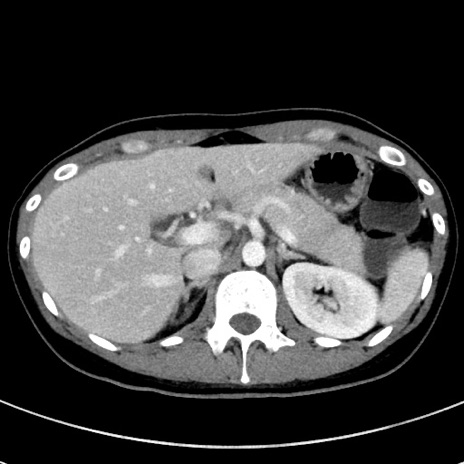

冠状断像

【症例】20歳代女性

【主訴】嘔吐、下腹部痛

【現病歴】昨日夕食後に嘔吐し下腹部痛が出現。本日になっても嘔吐持続し改善しないため来院。

【身体所見】意識清明、BT 37.2℃、BP 108/67mmHg、腹部:平坦、やや硬、下腹部正中から右にかけて圧痛あり、反跳痛軽度あり、tapping pain(+)。

【データ】WBC 13600、CRP 14.94